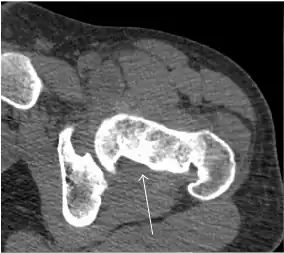

Synovial chondromatosis can be confidently diagnosed by X-ray when calcified cartilaginous chondromas are seen. However, other synovial proliferative processes, such as pigmented villonodular synovitis, require MRI for accurate diagnosis, although noncalcified synovitis can be suspected in radiographs by indirect signs, such as soft tissue swelling and/or erosions in the femoral head, femoral neck, or acetabulum (Figure 7).[1]

Figure 7:

-

Axial CT image of pigmented villonodular synovitis eroding the posterior cortex of the femoral neck.[1] -